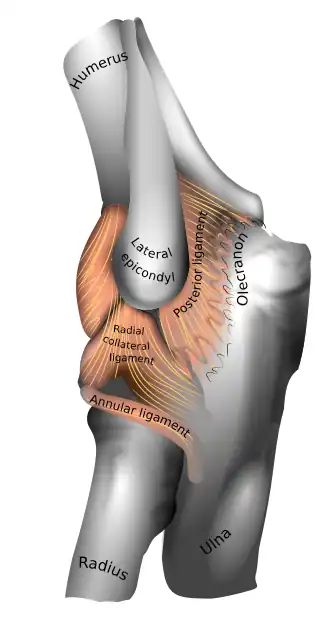

Ligaments

Left: anterior and ulnar collateral ligaments

Right: posterior and radial collateral ligaments

The elbow, like other joints, has ligaments on either side. These are triangular bands which blend with the joint capsule. They are positioned so that they always lie across the transverse joint axis and are, therefore, always relatively tense and impose strict limitations on abduction, adduction, and axial rotation at the elbow.[8]

The ulnar collateral ligament has its apex on the medial epicondyle. Its anterior band stretches from the anterior side of the medial epicondyle to the medial edge of the coronoid process, while the posterior band stretches from posterior side of the medial epicondyle to the medial side of the olecranon. These two bands are separated by a thinner intermediate part and their distal attachments are united by a transverse band below which the synovial membrane protrudes during joint movements. The anterior band is closely associated with the tendon of the superficial flexor muscles of the forearm, even being the origin of flexor digitorum superficialis. The ulnar nerve crosses the intermediate part as it enters the forearm.[8]

The radial collateral ligament is attached to the lateral epicondyle below the common extensor tendon. Less distinct than the ulnar collateral ligament, this ligament blends with the annular ligament of the radius and its margins are attached near the radial notch of the ulna.[8]